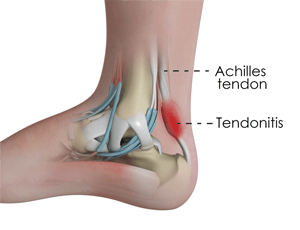

1. Tendinitis

Peradangan tendon (yang menghubungkan otot betis ke telapak kaki) karena peregangan berlebihan.